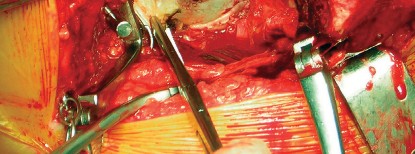

الخلاصة الطبية الشاملة: يُعتبر طول عمر مكون الحُق الأسمنتي في مفصل الورك الصناعي حجر الزاوية لنجاح جراحة استبدال مفصل الورك الكلي. يعتمد هذا النجاح بشكل كبير على التخطيط الدقيق قبل الجراحة، والتغطية الكافية من عظم المريض السليم، والتثبيت الأمثل للمكون بتقنيات أسمنتية حديثة. تتضمن الجراحة تقييمًا معمقًا لجودة العظم، إزالة دقيقة للنتوءات العظمية، وتطبيق مادة الأسمنت الطبي الحيوي لضمان تثبيت قوي ومستقر للحُق، مما يكفل الاستقرار والديمومة طويلة الأمد للمفصل الصناعي. مع المتابعة الدورية والالتزام بالبرنامج التأهيلي، يمكن للمرضى التمتع بنتائج ممتازة ونوعية حياة محسنة لسنوات عديدة. في صنعاء، يبرز الأستاذ الدكتور محمد هطيف كخبير رائد في هذا المجال، حيث يجمع بين الخبرة العميقة والتقنيات المتطورة لتقديم أفضل رعاية جراحية.

تُعد جراحة استبدال مفصل الورك الكلي (Total Hip Replacement - THR) من الإجراءات الجراحية الرائدة التي أحدثت ثورة في علاج آلام الورك المزمنة وتحسين القدرة الحركية للملايين حول العالم. ضمن هذا الإجراء المعقد، يلعب "مكون الحُق الأسمنتي" (Cemented Acetabular Component) دوراً محورياً في تحقيق الاستقرار والديمومة للمفصل الصناعي. إن تحقيق "طول عمر مكون الحُق الأسمنتي" ليس مجرد هدف تقني، بل هو وعد للمريض بحياة خالية من الألم، مليئة بالنشاط، وذات جودة عالية لسنوات طويلة بعد الجراحة.